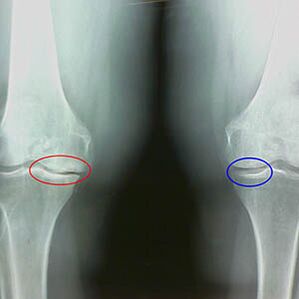

Ο βαθμός αρθρέματος καθορίζεται από το x -RayΑνταλλαγή συμμετοχής στην παθολογική διαδικασία των οστών. Η αλλαγή τους δείχνει ότι το μυϊκό σύστημα είχε ανισορροπία για 5 έως 10 χρόνια. Συνήθως οι άνθρωποιΒιώνετε επώδυνο πόνο για αρκετά χρόνια.

Το δεύτερο στάδιο της οστεοαρθρίτιδας θεωρείται απλό. Η εικόνα X -Ray δείχνει σημαντικά σπόρια οστών, αλλά ο χόνδρος δεν επηρεάζεται. Η ποσότητα του αρθρικού υγρού μειώνεται, αλλά μετά από μακρά συμπτώματα πόνου με μεγάλο περπάτημα και τρέξιμο, η δυσκαμψία στην άρθρωση και ο πόνος όταν κάμπτονται και στη θέση στα γόνατα εμφανίζονται.

Χαρακτηριστικά πρώιμης ακτίνας X του δεύτερου σταδίου της αρθρθείσας γόνατος:

- Οι αιχμηρές άκρες των εσωτερικών φυματίων στην κνήμη, στις οποίες συνδέεται η διασταυρούμενη ζώνη.

- Στενότητα του κοινού χάσματος στη μέση πλευρά.

- Οι αιχμηρές άκρες του κονδύλου των οστών στις μέσες πλευρές, λιγότερο συχνά στο πλάι - ανάλογα με την ανάπτυξη του βαλγού ή την παραμόρφωση της σύνδεσης παραλλαγής.

Για το δεύτερο στάδιο στο Larsen Η στένωση του κοινού χάσματος κατά περισσότερο από 50% είναι χαρακτηριστικήΩστόσο, αυτό μπορεί να ελεγχθεί μόνο στη δυναμική ή σε σύγκριση με ένα αδιάλειπτο των αρθρώσεων.

Η εικόνα x -ray δείχνει την παρουσία οστεοφυτών, μια αλλαγή στο διάστημα μεταξύ των οστών και των οστών της κνήμης, γεγονός που υποδεικνύει την απώλεια χόνδρου στο γόνατο. Μερικές φορές οι ακτίνες Χ των αρθρώσεων γόνατος δείχνουν σημαντικά σημάδια φθοράς χόνδρου, αλλά οι ασθενείς δεν έχουν σημαντικό πόνο.Αντίθετα, η αρθρίτιδα του πρώτου σταδίου μπορεί να διαταράξει τη λειτουργία του γόνατοςΗ αιτία του πόνου είναι οι υποτονικοί μύες.